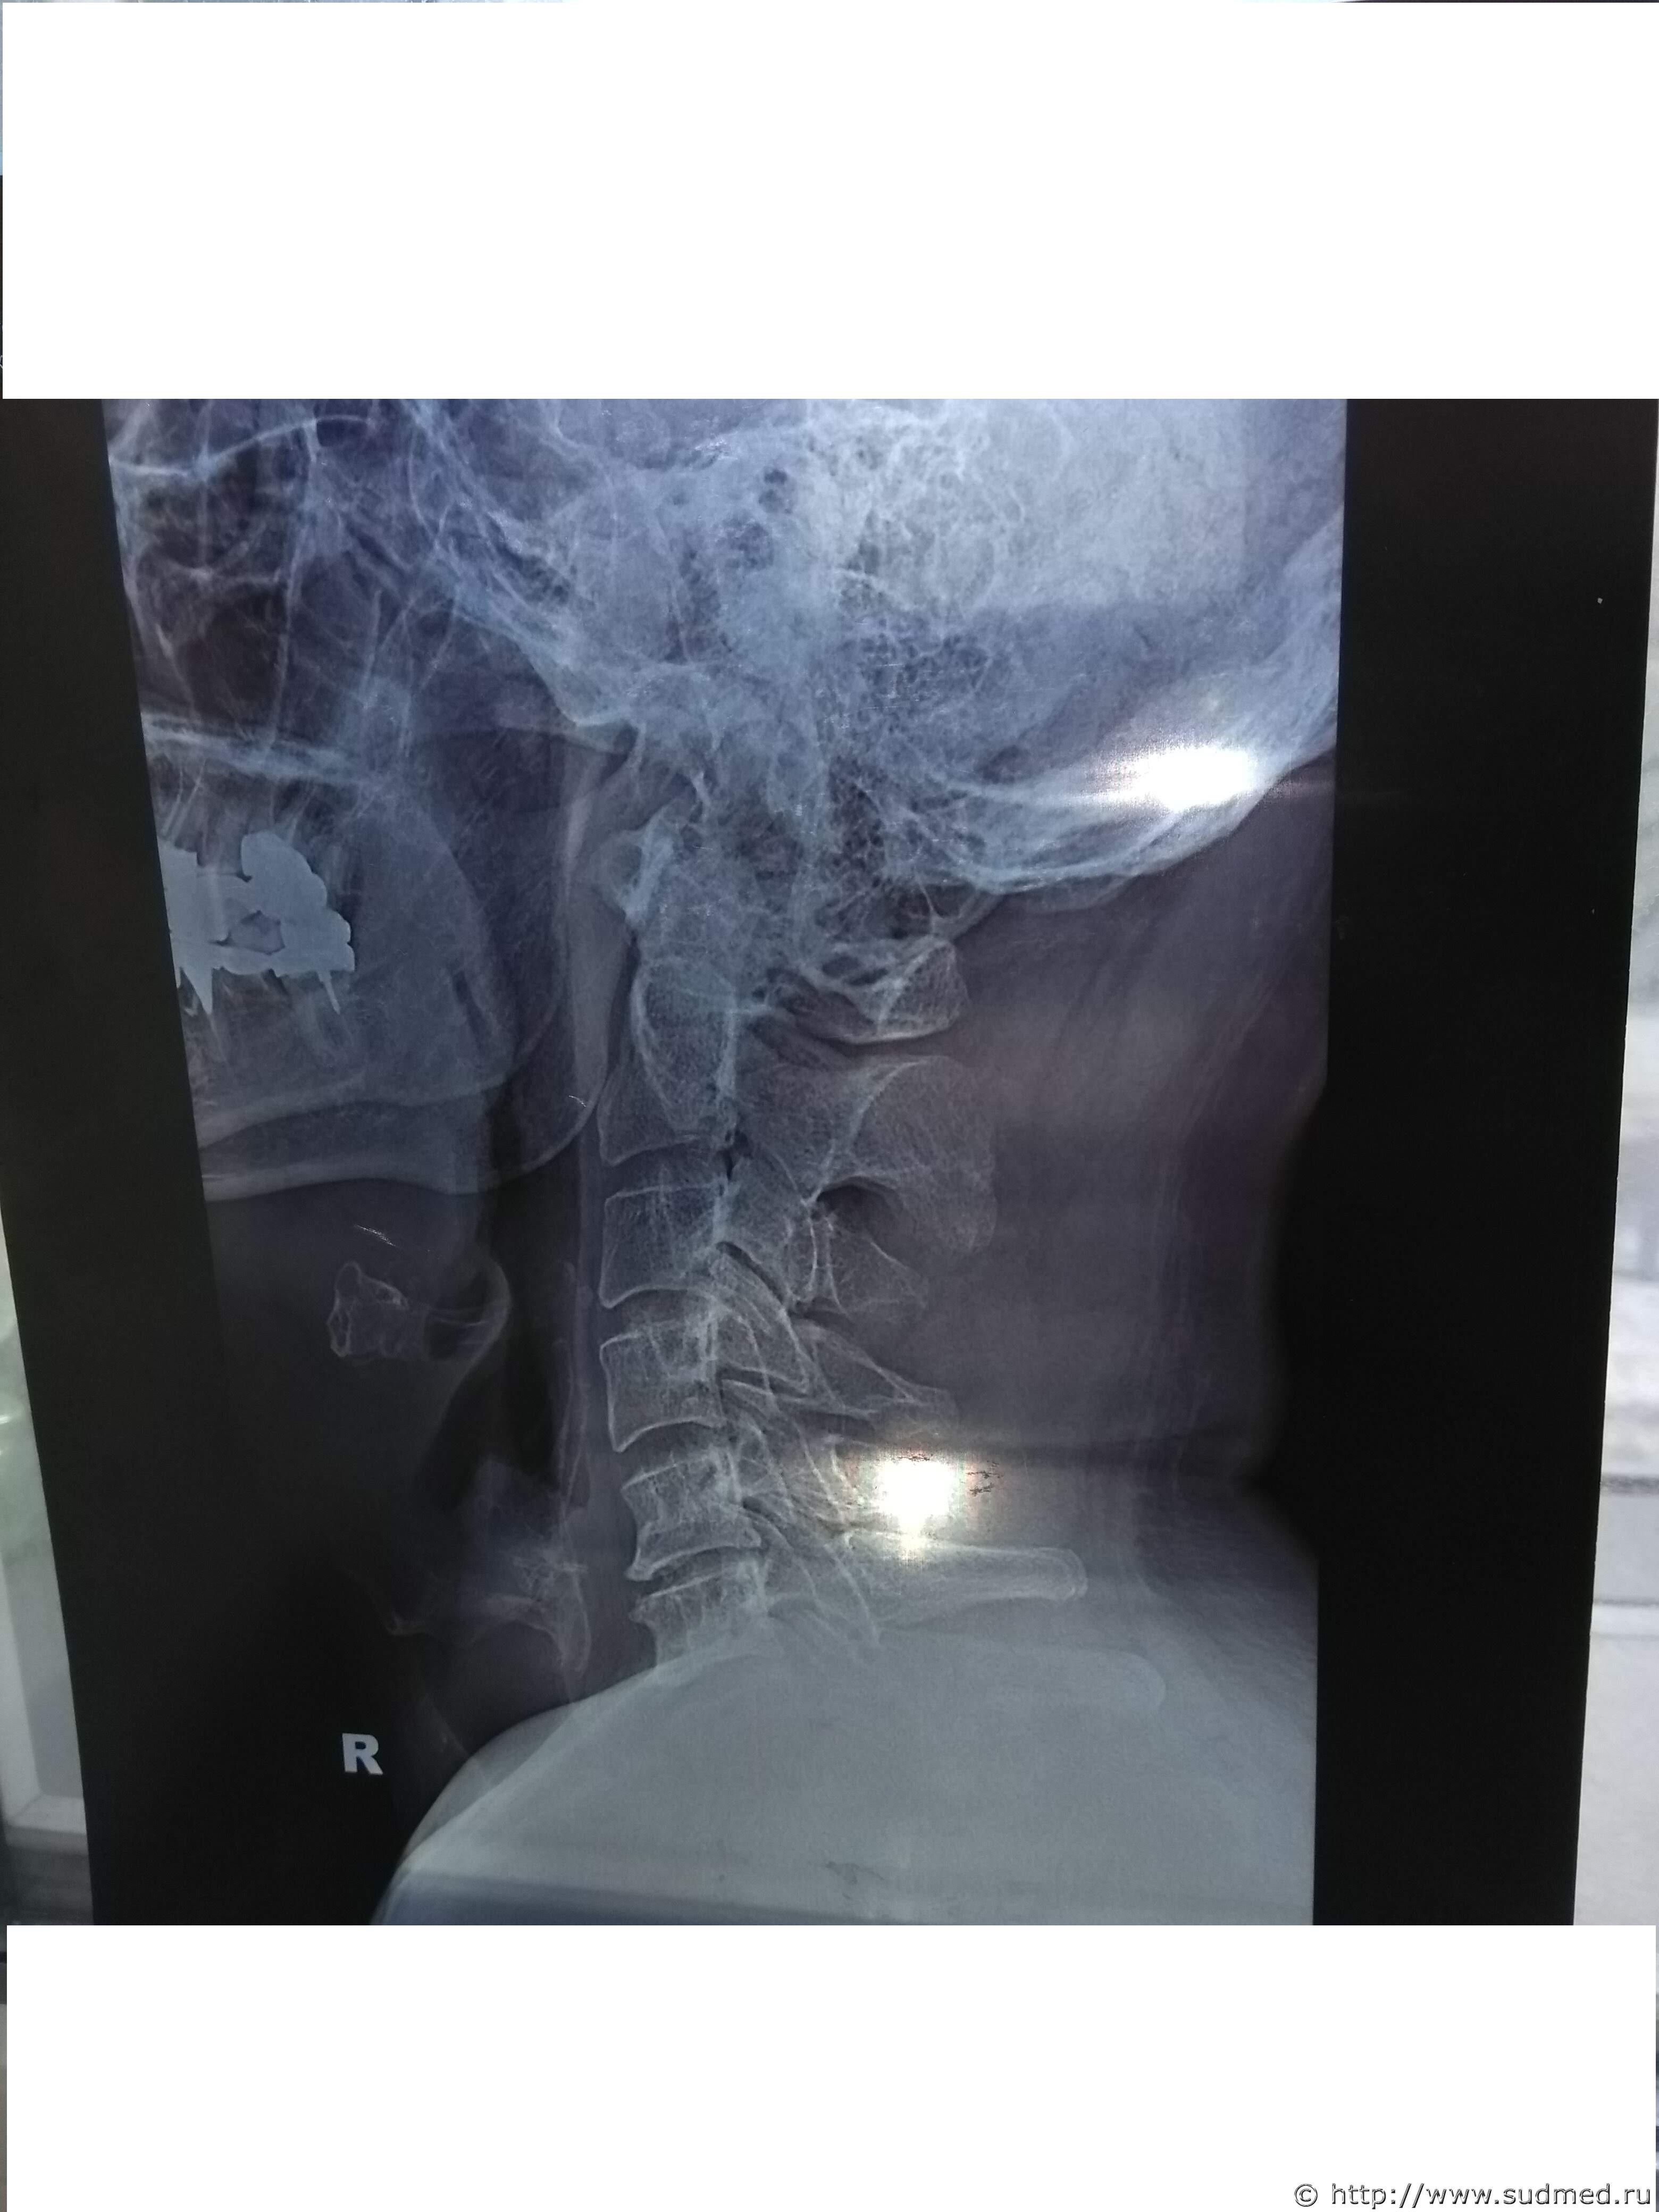

Какие повреждения видны на этой фототаблице?

Похоже на перелом щитовидного хряща, но утверждать не берусь: качество изображений низкое.

3. Не идеально ровная. Ход линии перелома зависит, в т.ч. от свойств самого хряща, а эти механические, прочностные свойства могут заметно варьировать: анатомически нормальный хрящ, более свойственный молодому возрасту, отличается от островчато или тотально оссифцированного хряща и т.д. В любом случае края "свежего" перелома имеют более "неровный" вид, чем сглаженные края перелома многонедельной-многолетней давности. Если есть возможность сопоставить два или более снимков (серий снимков), выполненных вскоре после травмы (в пределах первой недели или около того) и через несколько недель и/или месяцев, будет наблюдаться динамика: края отломков сгладятся, щель перелома станет завуалированной, частично прослеживаемой, в краях отломков появятся неравномерные изменения за счет очагов фиброза и оссификации.

6. Правильно писали. Стандартные рентгенограммы шейного отдела позвоночника практически не показывают хрящей шеи. Для такого исследования нужны специально и тщательно подобранные условия рентгеновского исследования. В абсолютном большинстве случаев в лечебных учреждениях этим "не заморачиваются". МРТ, КТ, УЗИ (убывание в плане информативности) лучше, чем "обычные" рентгенограммы шейного отдела позвоночника, рутинно выполняемые в больнице или поликлинике. (Идеальные условия для исследования хрящей гортани нам предоставляет труп - есть возможность непосредственно изучить их, в т.ч. с увеличением, проследить и проанализировать каждое повреждение, в т.ч. четко определить "старое" оно или "свежее").

1. Рентгенограммы бывают разные. В первую очередь это зависит от условий съемки. Обычная цель съемки области шеи - исследование состояния шейных позвонков. В таком случае мягкие и хрящевые ткани шеи - помеха для визуализации костных структур. Маскирующее влияние этой помехи устраняется соответствующими параметрами рентгеновского исследования. Рентгеновское исследование хрящей гортани - отдельная и не очень простая задача лучевой диагностики. Не стоящая "на потоке" в лечебных учреждениях. В Вашем случае такие рентгенограммы сделаны.

Коллеги оч.добросовестно подошли к работе. Не поленились назначить и выполнить соответствующие рентгенограммы. Частенько ленятся это делать. Или делают МРТ.

Между тем врач рентгенолог на суде сказал:

1. Снимок сделан для исследования костных структур шеи. Объясняется тем, что в центре снимка находится позвоночник, а не гортань. У рентгеновского аппарата два режима, один для исследования костных структур, второй для исследования мягких тканей.

2. На рентгеновском снимке не видно щитовидного хряща. Т.е. получается как в одном фильме. Ты суслика видишь. Нет. А он здесь есть.